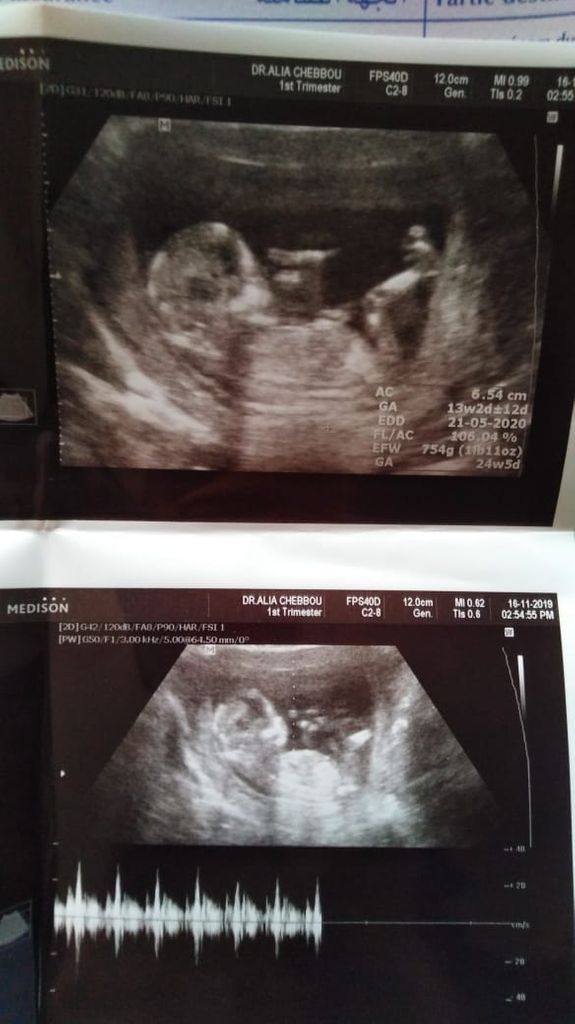

Ultrasounds may reveal sex organs by 14 weeks but they aren t considered fully accurate until 18 weeks. The more body tissue the ultrasound waves must travel through the fuzzier the images may be. A mother s weight also affects our ability to predict gender. The 2016 study i mentioned found that a body mass index below 23 8 was the best cutoff value for gender prediction at 11 to 13 weeks.

Alphabiolabs baby gender test allows you to find out whether you are having a baby boy or a baby girl from just 8 weeks into your pregnancy. 1 risk of miscarriage. The test is also known as cell free dna screening cfdna. By 13 weeks after all you can learn your baby s sex via an ultrasound with almost perfect accuracy.

Yes cells are taking from the placenta. At 7 weeks male baby 95 4 female 98 6. If you have a prenatal blood test nipt you may be able to find out your baby s sex as early as 11 weeks of pregnancy. As an aside my skepticism regarding tests using cffdna to determine fetal sex does not extend to the cffdna based screens for the 3 most common trisomies trisomy 13 trisomy 18 and down s syndrome.